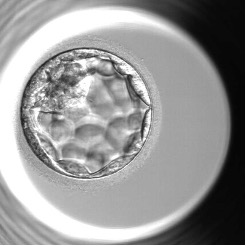

胚盤胞の特徴

胚盤胞になると、分割胚とは明らかに違い、胚には将来赤ちゃんになる内部細胞塊と将来胎盤になる栄養外胚葉があり、より生命の発生に近づいた構造を見せるようになります。評価はこれらの細胞を胚培養士が見た目での形態観察でおこない判定しています。

胚盤胞の様子

受精後5~6日目